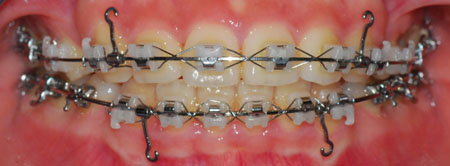

이번에 치과에서는 치아 상태 점검만 하고

저번 월치료와 같이 뺏다 꼈다 하는 고무줄을 걸기로 했어요.

고무줄을 잘 꼈다고 치과 쌤이 뿌듯해하시는 거 같았어여....(저만의 생각?!ㅎㅎ)

이제 발치공간을 줄이기 위해 고무줄을 더 열심히 걸어야 겠어욧!

전체 치아 사진 보여 드릴게요~